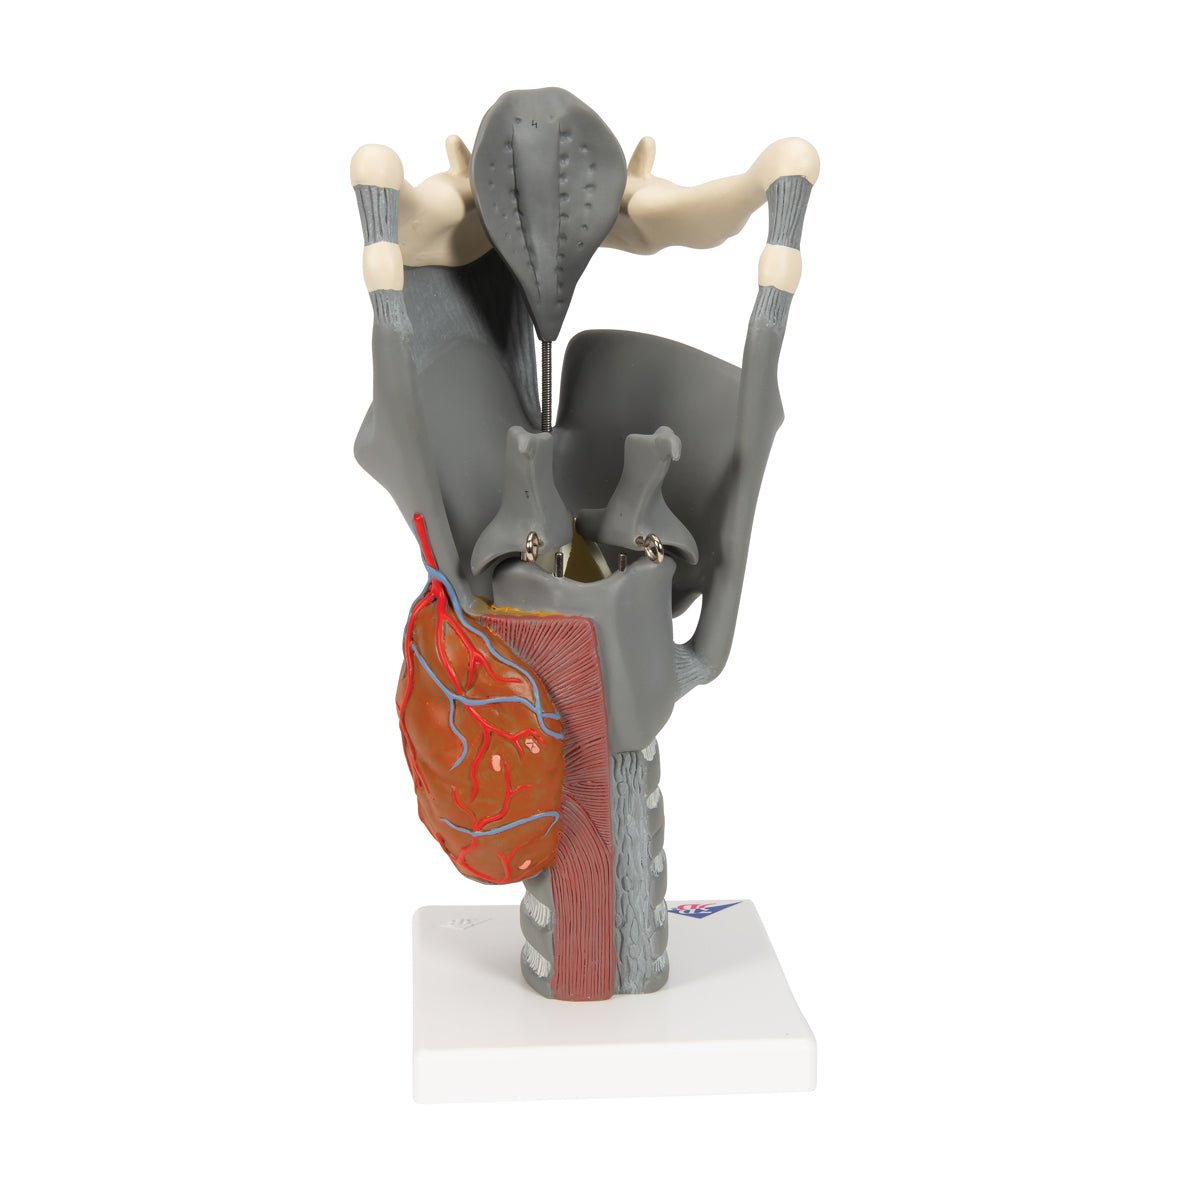

Salg af anatomiske modeller er det bærende element i eAnatomi, selvom vi også bruger mange ressourcer på at udvikle vores egne anatomiske materialer som fx plakater. Anatomiske modeller anvendes til forskellige formål og kan både vise afgrænset væv, organer samt organsystemer. Søger du en simpel model af knoglevæv eller måske en avanceret torso-model baseret på MRI teknologi, kan du finde det hele på eanatomi.com.